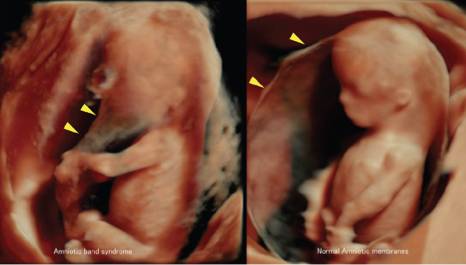

Диагностика

Обнаружить тяжи в амниотической жидкости можно с помощью ультразвукового исследования, которое проводится в начале второго триместра, хотя это не всегда удается. Нити могут быть настолько тонкими, что их сложно заметить на экране. Если у ребенка впоследствии будут выявлены деформации частей тела, то устанавливается соответствующий диагноз.

Если потребуется провести дополнительные исследования, то может быть назначено 3D-УЗИ, МРТ и эхокардиография плода. Эти процедуры необходимы для предотвращения серьезных последствий для здоровья малыша.